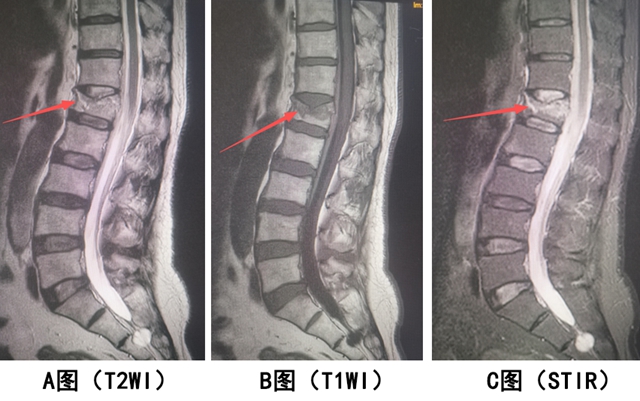

【案例2】患者男,腰背部间断性病痛,曾有腰部受伤史。作腰椎MRI检查,如下图。

腰椎 MRI 显示:L4 椎体呈楔形变(陈旧骨折的形态改变),但所有成像序列的信号都和正常椎体一致(无水肿,骨痂已愈合)。

结论:L4 椎体陈旧性压缩骨折。

关键:形态异常 + 信号正常(提示愈合已久,无水肿)。